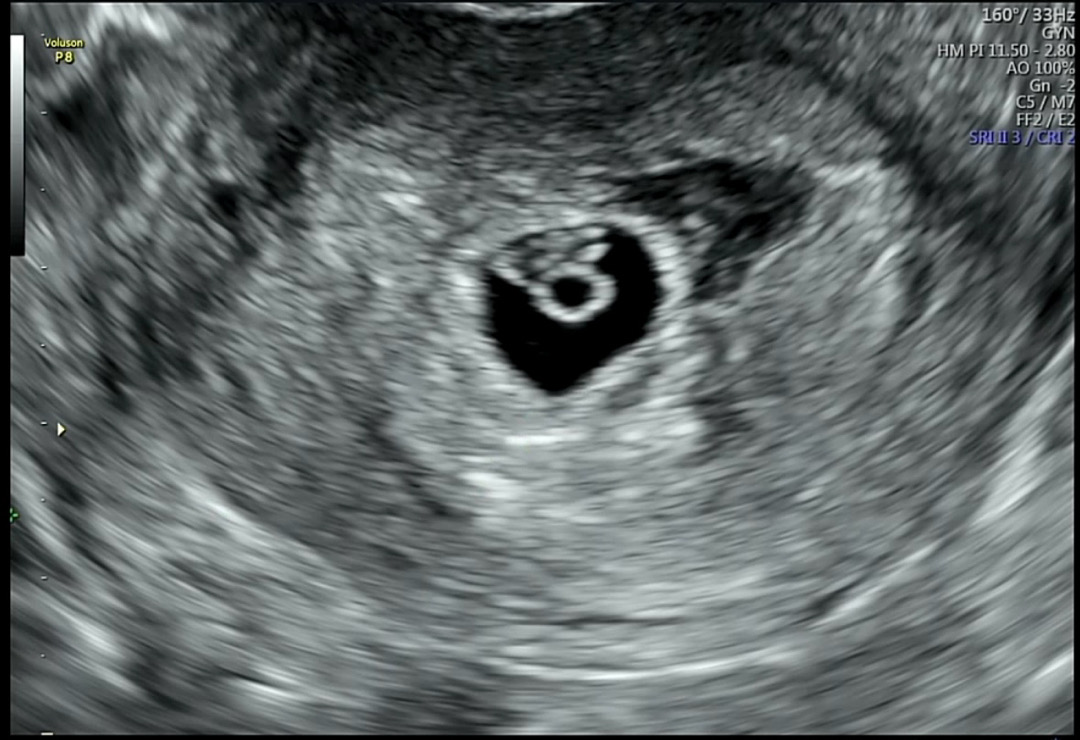

6주4일차 아기랑 난황 그리고 심장소리 듣고 왔어요 근데 아기는 주수에 맞게 잘컷는데 아기집이 작데요 ㅠㅠ 아기집은 1.2 아기는 0.66 일주일 넘게 차이가 난대요ㅠㅠ 갈때마나 조마조마하네요 아기집 키우는건 방법이 따로 없죠??